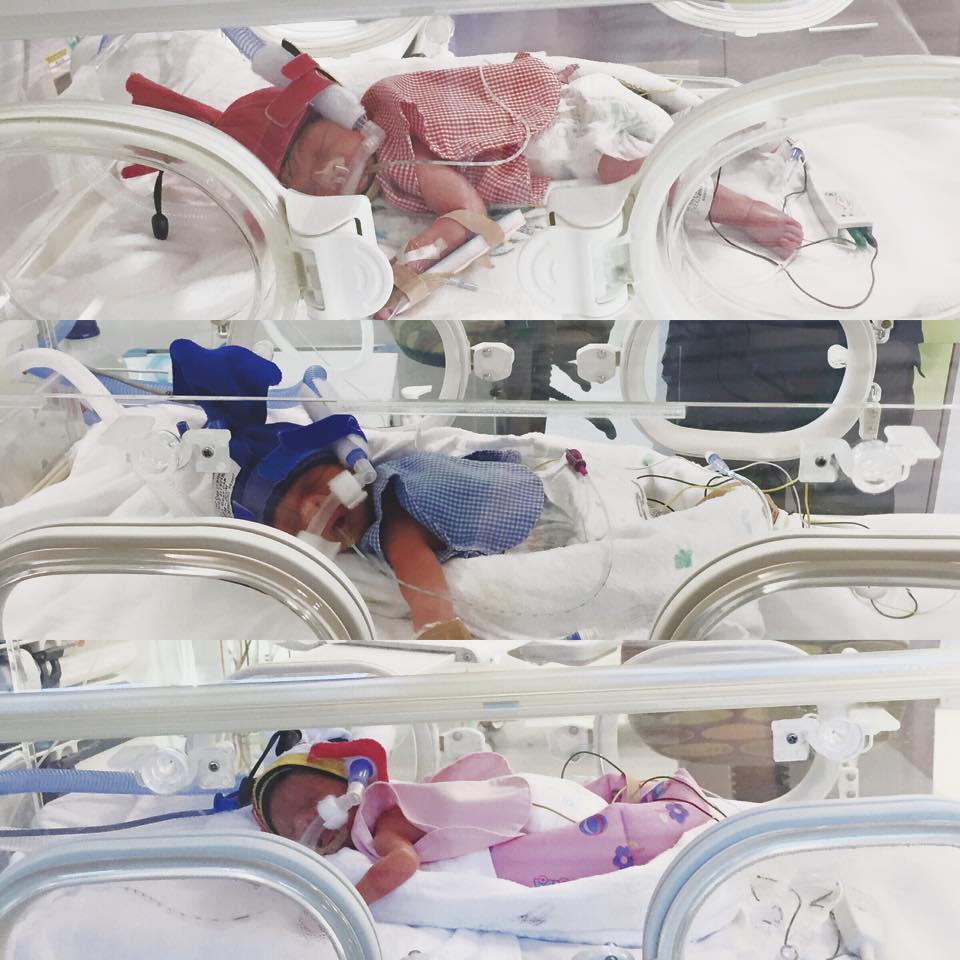

마침내, 클로이가 세쌍둥이를 출산했을 때, 아이들은 즉시 인큐베이터로 가서 집중 치료를 받았다.

다행히도 세 아이는 하루하루가 다르게 건강해졌다.

세 아이 중 가장 작은딸 Pearl은 세상과 용감하게 싸우고 살아났다.